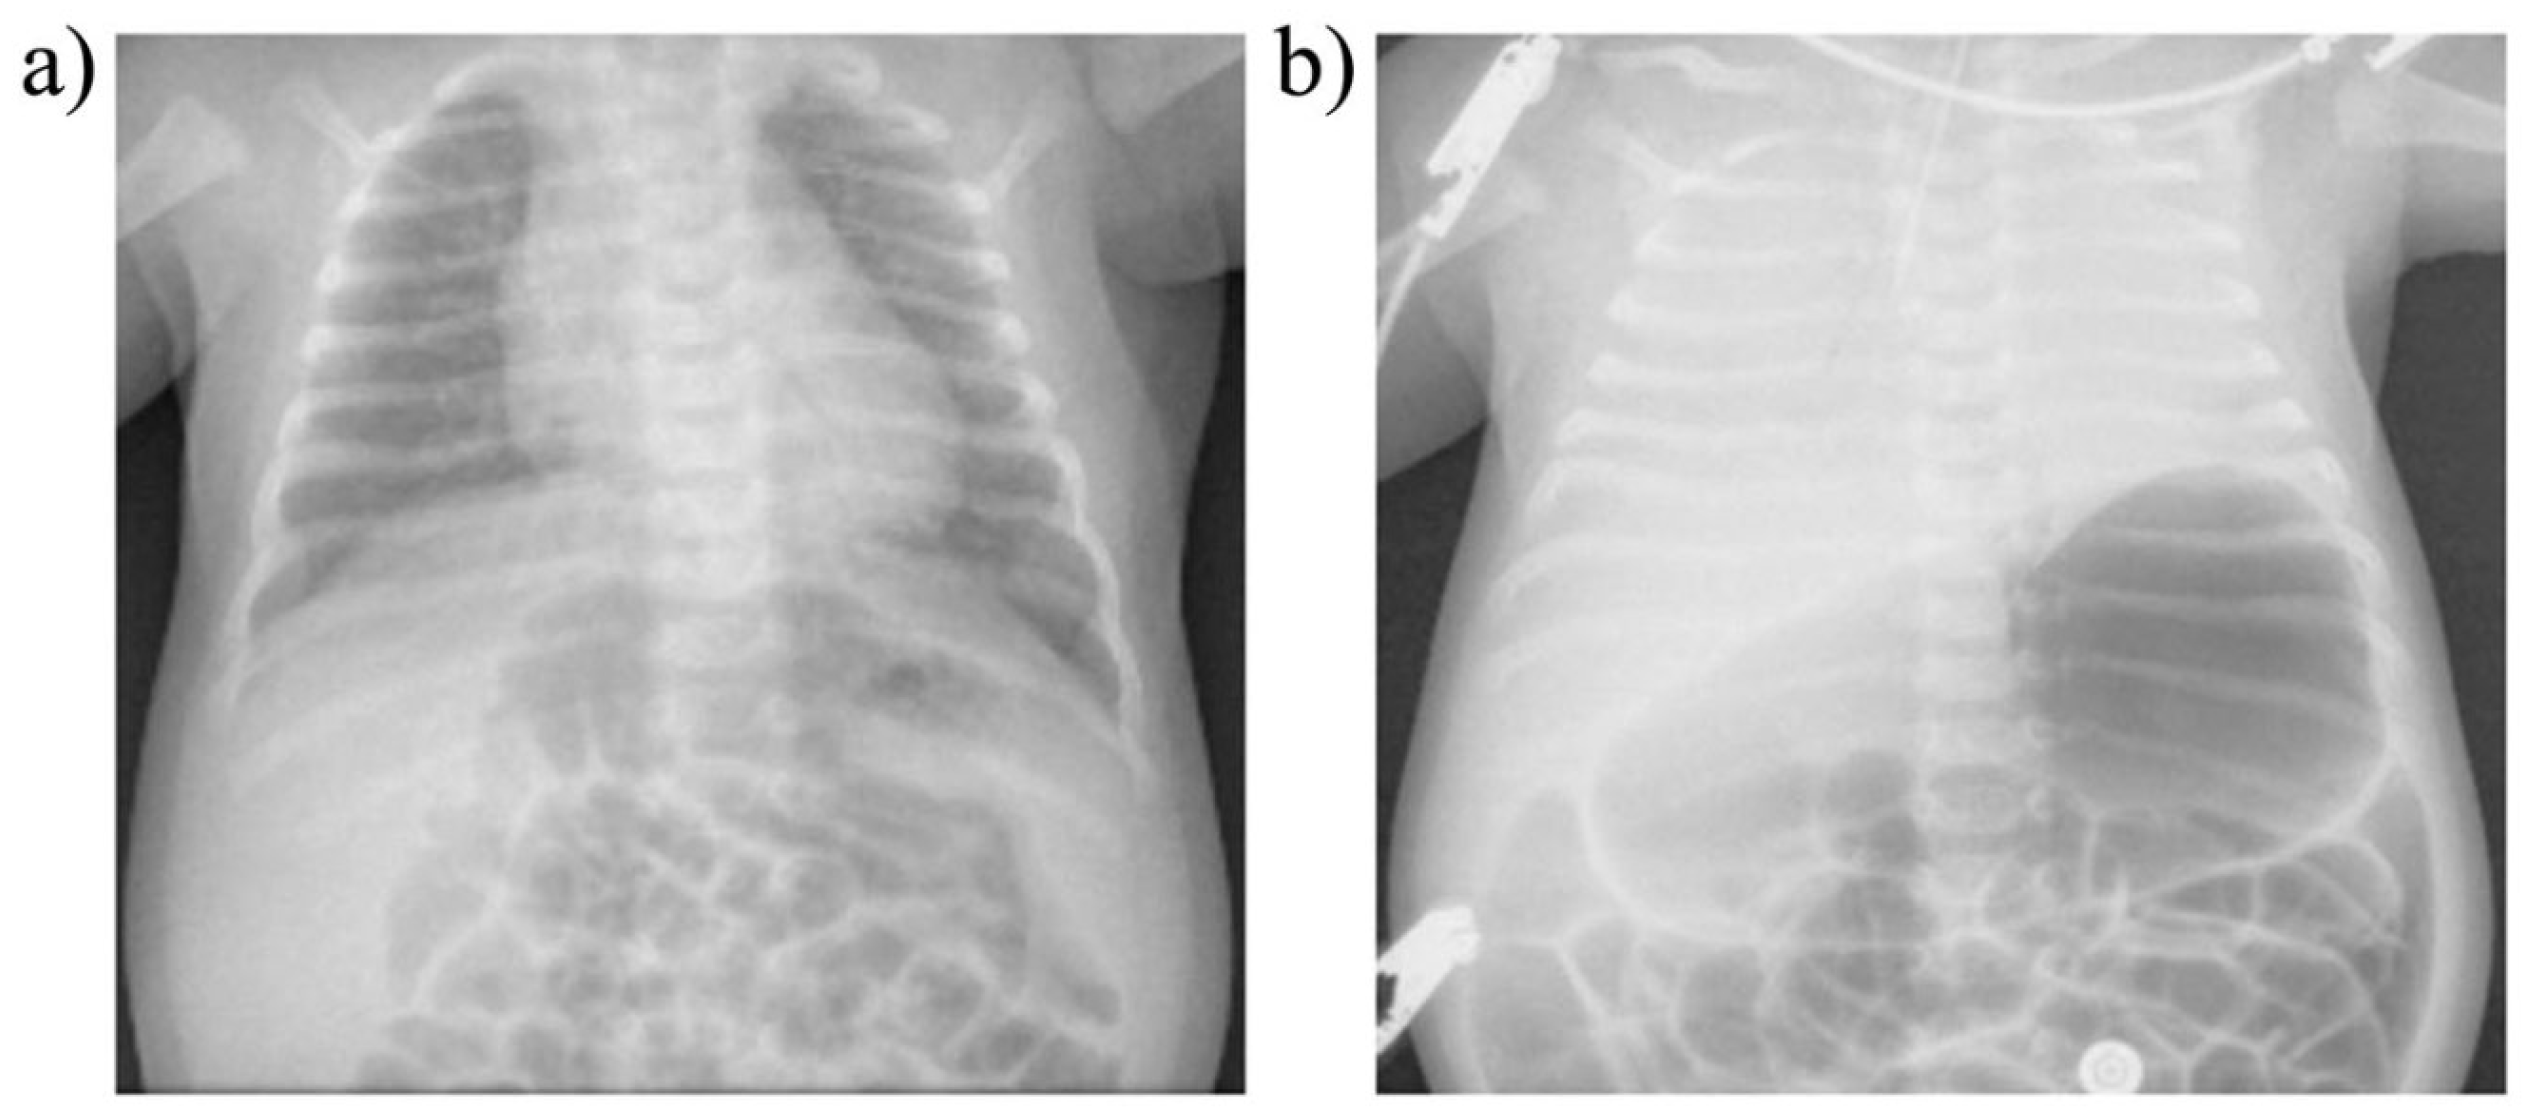

Figure 13 reveals significant abnormalities on chest X-ray that rapidly developed in a 40-day-old infant admitted with RSV. The baby, who had presented with fever, cough and wheezing, suddenly deteriorated with respiratory distress marked by hypoxemia, hypercapnia and respiratory acidosis. Terminal apnea and death occurred before intubation could be done. Complete opacification of both lung fields with an air-dilated stomach and proximal bowels developed in less than two hours. No explanation could be provided. Although diaphragm pathology was not reported, the clinical findings and X-ray changes were consistent with progressive diaphragm fatigue (insufficiency), sudden failure (respiratory arrest) and agonal airway obstruction by DCC. Terminal ineffective RAM efforts could have led to substantially negative intrathoracic pressures with resultant pulmonary shunting, edema, hemorrhage, and fluid extravasation. Also, intrapulmonary air could have been forced into the digestive tract, perhaps trapped by the putative esophageal hiatus clamp, leading to reduced pulmonary expansion from increased intra-abdominal pressure. By contrast, in MV patients, such findings have not been reported to our knowledge. This could be due to the reduced work of breathing averting DCC obstruction.